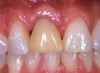

Fig 9. Initial placement of the provisional.

Figure 9